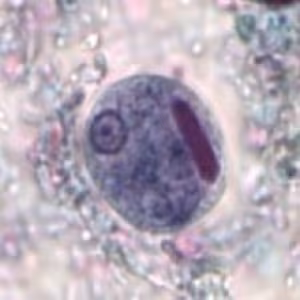

Case #497 – August, 2019

A 21-year-old exchange student from Nigeria presented to the University Clinic with a 3-day history of diarrhea, mild abdominal pain, loss of appetite, and fatigue. Stool samples collected in 10% formalin and Zn-PVA fecal preservatives were sent to the laboratory for analysis. Figures A–D show organisms seen by the technologist in a trichrome-stained slide of the Zn-PVA sample. The organisms ranged in size from 12-26 μm. What is your diagnosis? Based on what criteria? What other testing, if any, would you recommend?

Figure A